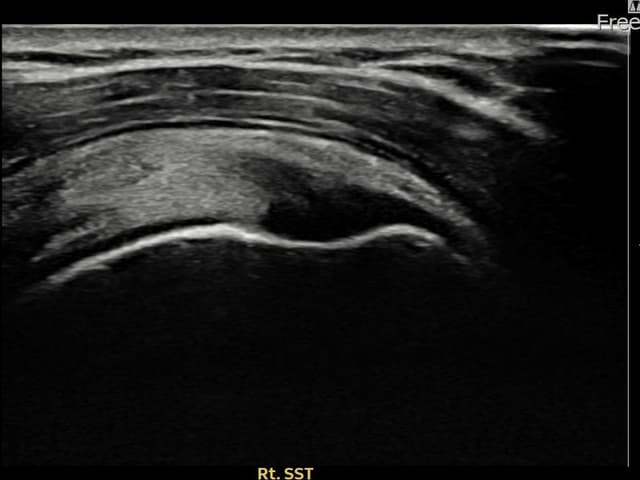

実際の患者様の施術前後の超音波画像。

手術なしで実現できる回復をご確認ください。

[経過期間: 23.10.05~23.12.07]

[縫縮術] 超音波検査にて右 棘上筋腱 付着部部分断裂(10mm × 4mm (腱厚の約42%欠損))を確認。縫縮術施行後、腱の連続性が回復し、日常生活に復帰されました。